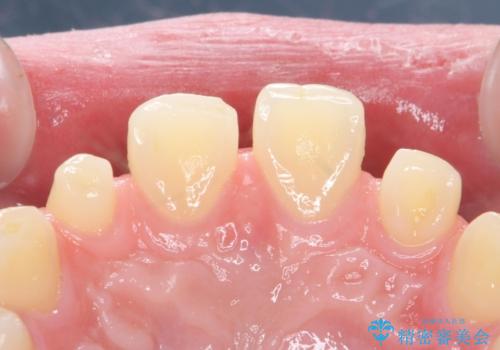

- 前歯の隙間を埋めたいとのことで来院された患者様です。

矯正治療とかぶせ物での治療どちらともご提案したところ、かぶせ物での治療をご希望されたためクラウンでの審美性回復を試みることとなりました。

今回のように、元の歯が小さすぎる場合は矯正治療での審美性回復が難しいことがあります。